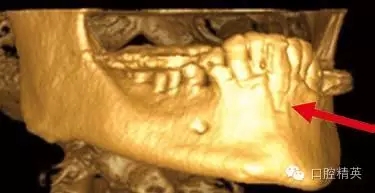

圖1c:術后用ICATCBCT進行三維立體效果再現(xiàn),顯示種植體穿入上頜竇的實踐情況

圖3a:術后的三維影像重建給外科醫(yī)生對手術入路的回顧以提示。對于這一病例進行了Caldwell-Luc術式,用球鉆在上頜竇側(cè)壁做一窗口,直接入路取出種植體。

其他研究也報道過,對于這種病例,唯一的選擇是用根管顯微鏡或Caldwell Luc技術從上頜竇中取出種植體。有些文章報道了如何處理進入上頜竇的種植體,但很少從預防的角度來談這個問題,其實很簡單,術前應該應用CBCT成像檢查。

另外一個棘手的問題和上頜骨前部的解剖結(jié)構(gòu)有關。(圖3)這種病例,從臨床檢查上看,上頜骨量非常豐富,頜骨矢狀斷面呈三角形,符合Scott Ganz醫(yī)生所描述的“三角形骨”理論。這一理論幫助確定牙槽骨固有形態(tài),判斷最佳的種植體植入位置。

如這個病例展示的,CBCT斷層掃描揭示了牙槽骨根方的凹陷。這樣就避免了術中的意外,醫(yī)生可以在術前完善的計劃,向患者交代清楚手術方法、風險、以及植骨所需增加的相應費用等問題。在兩維的放射影像中是無法預先觀察到這個問題的。僅使用兩維放射診斷帶來的另一個并發(fā)癥是種植體折斷。(圖4)前面提過,兩維曲面斷層影像難以獲得精確定位,有的醫(yī)生為了避免損傷下頜神經(jīng)管而應用短種植體。這樣做的結(jié)果是增加了修復體-種植體長度比,隨著時間的流逝會造成骨吸收,最終可能導致種植體折斷。